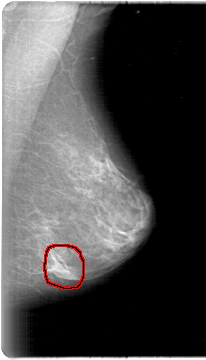

FILE: D_4024_1.LEFT_MLO.OVERLAY

TOTAL_ABNORMALITIES 1

ABNORMALITY 1

LESION_TYPE MASS SHAPE LOBULATED MARGINS CIRCUMSCRIBED

ASSESSMENT 0

SUBTLETY 3

PATHOLOGY BENIGN

TOTAL_OUTLINES 1

BOUNDARY